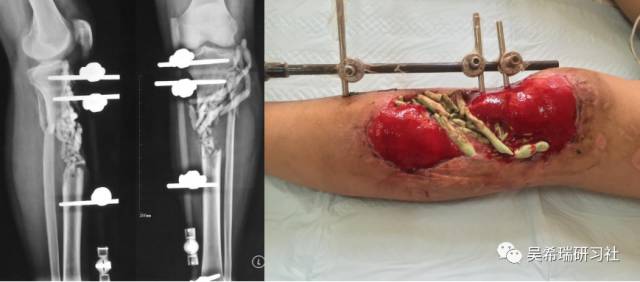

车祸伤多发伤胫骨近端开放骨折软组织缺损右上肢截肢

TIPS:开放骨折外固定游离植皮缩小伤口搬移+半开放植骨半开放植骨=骨水泥技术+开放植骨+骨搬移横向、前后调整搬移骨块下地走路刺激骨愈合早期关节功能锻炼